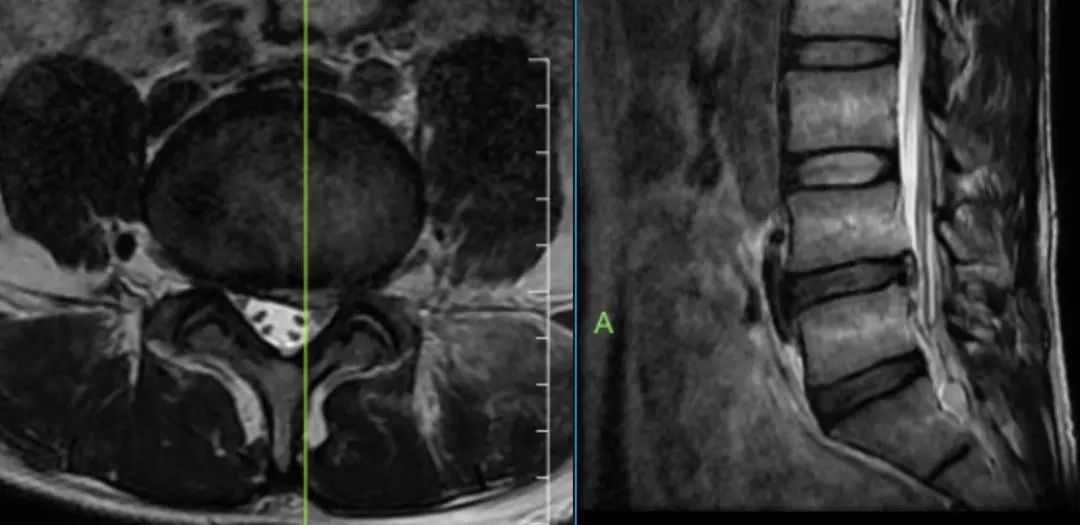

术前及术后核磁共振影像对比发现,术后突出的间盘(髓核)完全去除效果良好,完全保留关节突关节,预计3月后,完整保留的纤维环和后纵韧带将完全回缩。

术前影像

术后影像